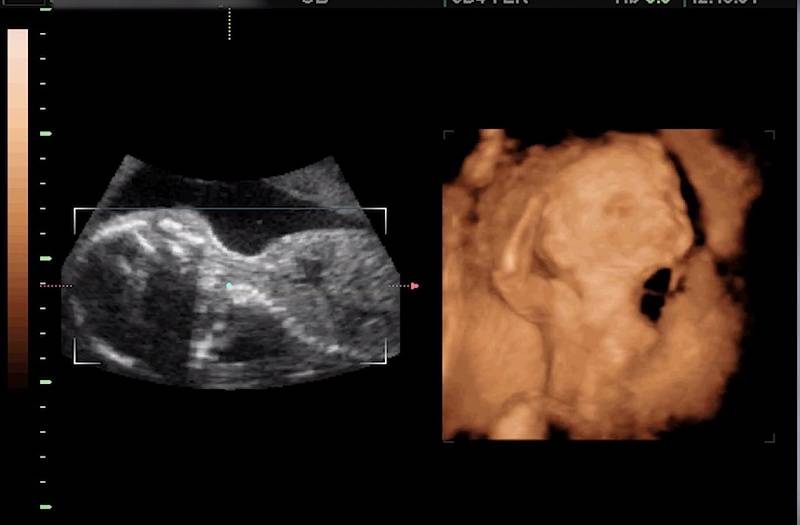

Буква D обозначает слово Dimension – «измерение». Когда мы слышим слово ультразвук, то обычно всем на ум приходит такая черно-белая картинка. Это как раз то, что принято называть 2D. Можно сказать, что это стандартный режим от которого отталкиваются все остальные режимы? и какое исследование вы бы вначале не выбрали, в любом случае, в этом режиме пройдет большая его часть. Большинство параметров оцениваются именно в нем, такие как: измерение размеров плода, оценка строения головного мозга, внутренних органов и даже оценка работы сердца в реальном времени. Обычно это не самый интересный для “непосвещенных” режим, но в определенных плоскостях, картинка может быть достаточно понятной любому.

3D режим, в своем названии содержит еще одно измерение. И если 2-хмерный режим подразумевает плоскость, то 3-мерный – объем. И речь идет не только, и не столько об изображении, которое мы видим на экране, сколько о типе фаила в приборе. Объем достигается более совершенной компьютерной обработкой и механическим движением пьезокристалла внутри датчика. Получив 3-хмерный объем, его можно разложить на любое количество 2-хмерных плоскостей и зачастую получить нужные срезы, получить которые может быть в 2D режиме затруднительно за счет положения плода. Параметры терминального и механического индексов ультразвука при этом остаются такими же, как и при 2-хмерном исследовании. Поэтому разговор о каком-то дополнительном воздействии на плод в этом режиме не имеет под собой серьезных аргументов. Единственный аргумент, который остается, это увеличение длительности исследования, однако, после получения нужного объемного фаила, зачастую, врач ультразвуковой диагностики продолжает его обработку на приборе уже с выключенным датчиком.

Сопоставьте: слева УЗИ 2d, а с правой стороны 3d

Если первые три вида – это знакомое всем двухмерное сканирование с чёрно-белым изображением, то 3D и 4D – совершенно иные способы исследования. Выполняются они при помощи современного оборудования, в результате получается объёмная и детализированная картинка.

3D УЗИ – это вид эхографии, при котором трёхмерная объёмная картинка формируется из двухмерных изображений. Сканирование позволяет определить пол малыша, рассмотреть его лицо и даже пальчики на руках и ногах. По сравнению с обычным двухмерным УЗИ никаких сверхвозможностей 3D-сканирование не даёт. Это не замена, а, скорее, дополнение к плановому сканированию. Но иногда объёмная картинка даёт возможность лучше рассмотреть некоторые детали. Например, на картинке можно увидеть, что лицо ребёнка сморщено. А это свидетельствует о кислородном голодании.